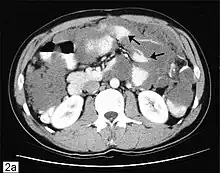

CT scanning is preferred to assess the extent of the tumor in the abdominopelvic cavity, though magnetic resonance imaging can also be used.[28] CT scanning can also be useful for finding omental caking or differentiating fluid from solid tumor in the abdomen, especially in low malignant potential tumors. However, it may not detect smaller tumors. Sometimes, a chest x-ray is used to detect metastases in the chest or pleural effusion. Another test for metastatic disease, though it is infrequently used, is a barium enema, which can show if the rectosigmoid colon is involved in the disease. Positron emission tomography, bone scans, and paracentesis are of limited use; in fact, paracentesis can cause metastases to form at the needle insertion site and may not provide useful results.[29] However, paracentesis can be used in cases where there is no pelvic mass and ascites is still present.[29] A physician suspecting ovarian cancer may also perform mammography or an endometrial biopsy (in the case of abnormal bleeding) to assess the possibility of breast malignancies and endometrial malignancy, respectively. Vaginal ultrasonography is often the first-line imaging study performed when an adnexal mass is found. Several characteristics of an adnexal mass indicate ovarian malignancy; they usually are solid, irregular, multilocular, and/or large; and they typically have papillary features, central vessels, and/or irregular internal septations.[31] However, SCST has no definitive characteristics on radiographic study.[33]

In advanced cancers, where complete removal is not an option, as much tumor as possible is removed in a procedure called debulking surgery. This surgery is not always successful, and is less likely to be successful in women with extensive metastases in the peritoneum, stage- IV disease, cancer in the transverse fissure of the liver, mesentery, or diaphragm, and large areas of ascites. Debulking surgery has usually only been done once[28] but a recent study has shown a longer overall survival in recurrent ovarian cancer when surgery combined with chemotherapy was performed compared to treatment with chemotherapy alone.[97] Computed tomography (abdominal CT) is often used to assess if primary debulking surgery is possible, but low certainty evidence also suggests fluorodeoxyglucose‐18 (FDG) PET/CT and MRI may be useful as an addition for assessing macroscopic incomplete debulking.[98] More complete debulking is associated with better outcomes: women with no macroscopic evidence of disease after debulking have a median survival of 39 months, as opposed to 17 months with less complete surgery.[26] By removing metastases, many cells that are resistant to chemotherapy are removed, and any clumps of cells that have died are also removed. This allows chemotherapy to better reach the remaining cancer cells, which are more likely to be fast-growing and therefore chemosensitive.[29]